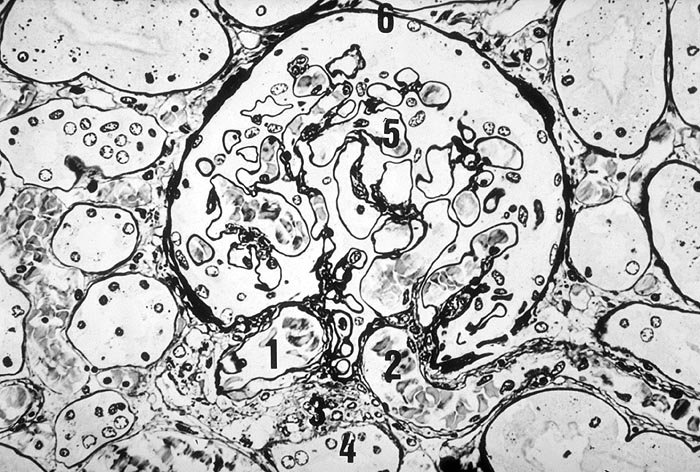

PathoPic ID 1603 - Normaler Glomerulus

Normaler Glomerulus

Normalbefund

Niere

Niere, Harnwege

1. Vas afferens

2. Vas efferens

3. Juxtaglomerulärer Apparat

4. Macula densa

5. Periphere Kapillarschlinge

6. Bowman Kapsel